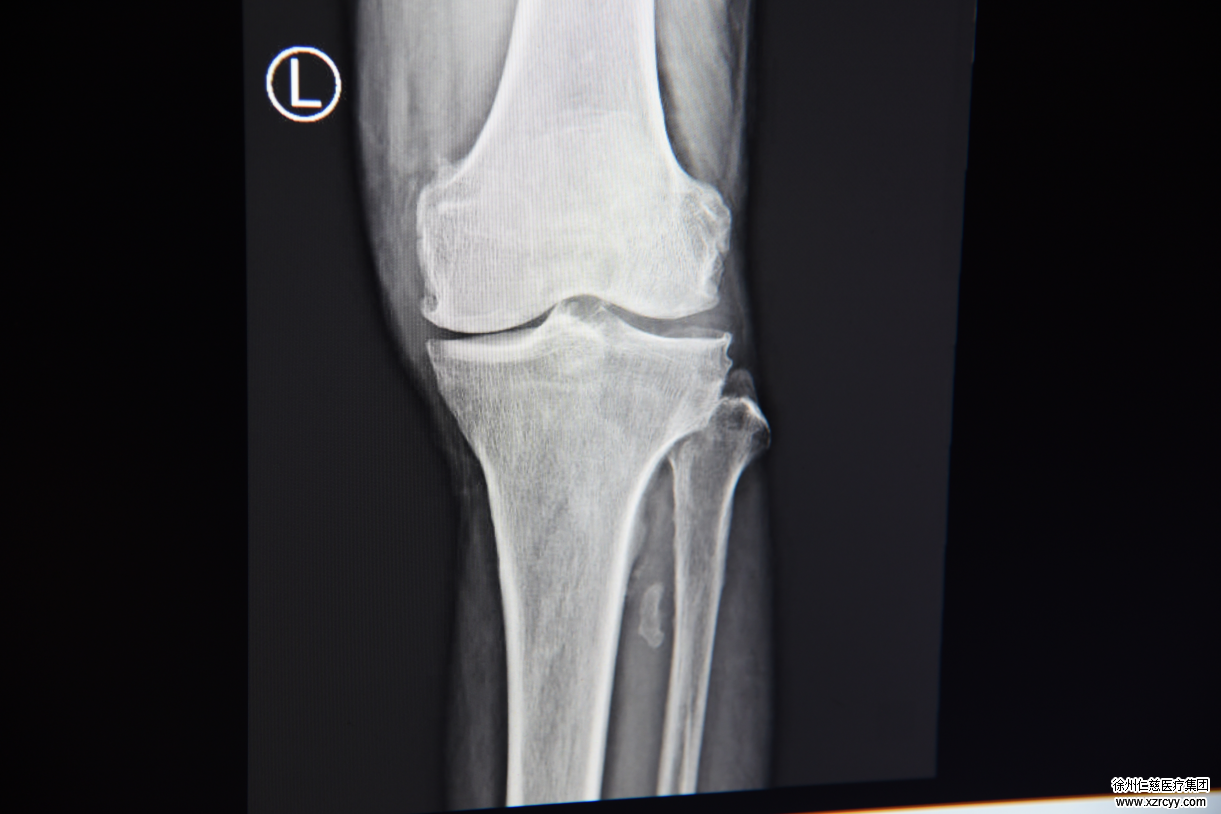

术前X片,关节两侧缝隙不同

连续疼痛让老人寝食难安,为了让老人不那么疼,家人带着马先生到betway在线登陆,希望医生给老人“打封闭针缓解疼痛”,接诊的betway在线登陆骨科蒋守海主任介绍:“老人检查受累关节可见关节肿胀、压痛,活动时有摩擦感和‘咔嗒’声,我们判定这个病人是骨关节炎。这种病疼痛感很强。打封闭只是暂时性的,并不能解决根本问题。在综合判断后,我们觉得老人可以接受关节矫正微创手术。”

术后腓骨截去1-2厘米,右侧支撑作用减轻,关节缝隙后期变的均衡

通过3公分左右的开口,将腓骨裁掉一公分,改变卸掉外侧支撑力,让内侧胫骨承重,这样内外侧受力就能均匀,不用置换关节就能起到良好的恢复效果。